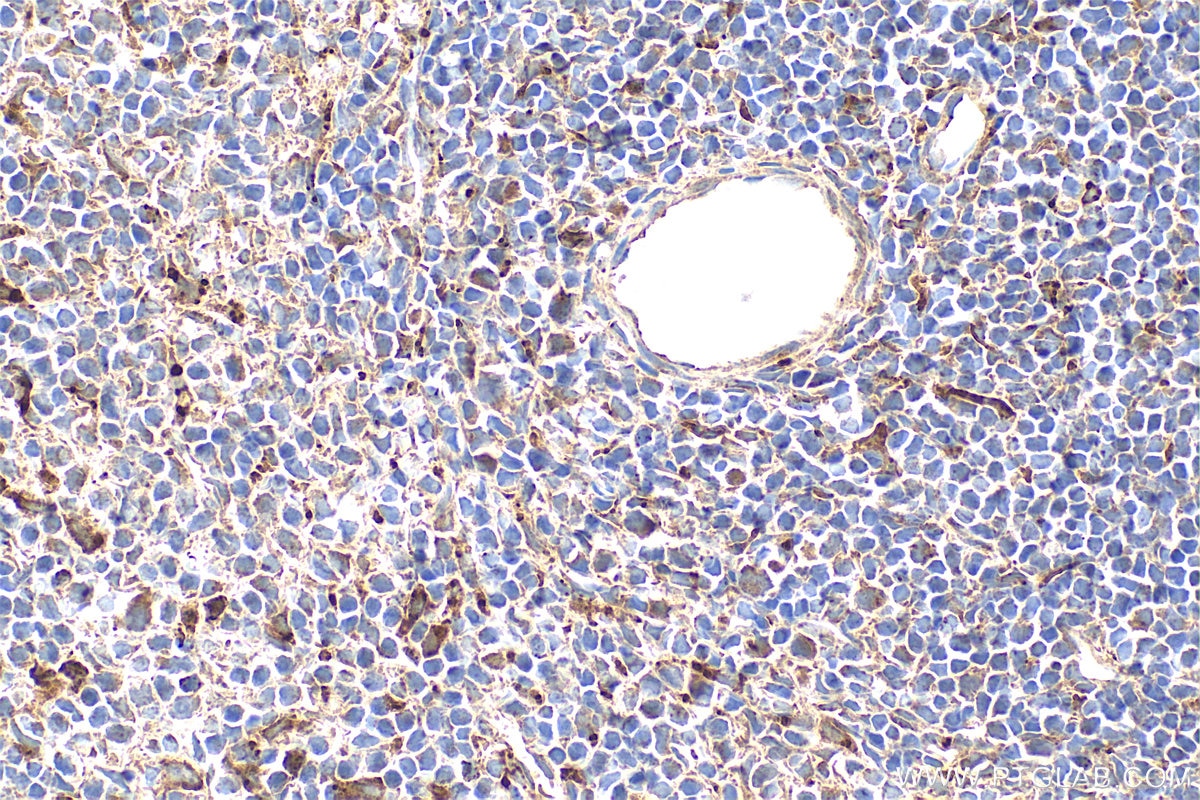

| Positive IHC detected in | rat kidney tissue, mouse spleen tissue, rat spleen tissue Note: suggested antigen retrieval with TE buffer pH 9.0; (*) Alternatively, antigen retrieval may be performed with citrate buffer pH 6.0 |

| Immunohistochemistry (IHC) | IHC : 1:50-1:500 |